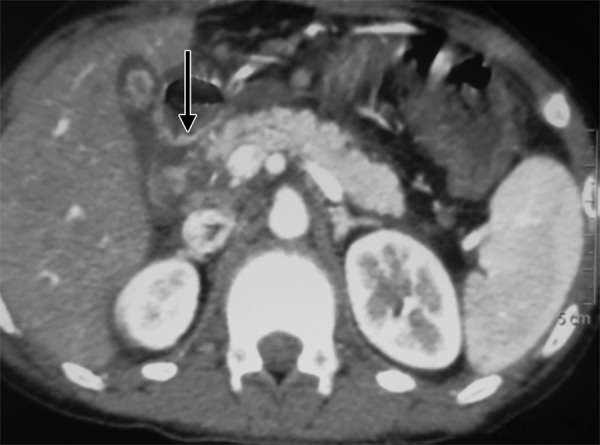

A 10-year-old girl was admitted in a private hospital for an acute abdomen. She presented with complaints of abdominal pain, distention, and fever. Preoperative ultrasound was suggestive of free fluid. Intraoperatively, there was bile in the peritoneal cavity, no bowel perforation and a rent in CBD, suggestive of biliary tract perforation. A drain was kept in the Morrison’s pouch, and she was referred to our institute for further management. At admission, the patient was stable in regard to hemodynamical parameters. The draining output was approximately 200 to 300 mL of bile per day. Contrast enhanced computed tomography (CECT) scan suggested discontinuity in the medial wall of suprapancreatic CBD extending proximally for a length of approximately 1.4 cm with an ill-defined collection in the Morrison’s pouch and mild free fluid in the peritoneal cavity (Fig. 1). Endoscopic retrograde cholangiopancreatography revealed a leak from CBD just below the insertion of cystic duct (Figs 2 and 3), and a 7 French stent was inserted with the tip beyond the leak. The abdominal draining was stopped and removed. The patient was gradually shifted to oral diet. She was discharged after 8 days, and her stent was removed after 8 weeks. She is doing well on follow-up.